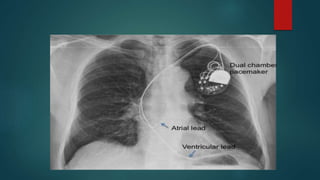

Technique of permanent pacing

 In permanent pacing, leads through the subclavian or cephalic vein.

 Leads positioned in the right atrial appendage for atrial pacing and right

ventricular apex for ventricular pacing.

 The pulse generator lies in the subcutaneous pocket below the clavicle.

CHEST X-RAY

Lead position

Paced position

Type of CIED